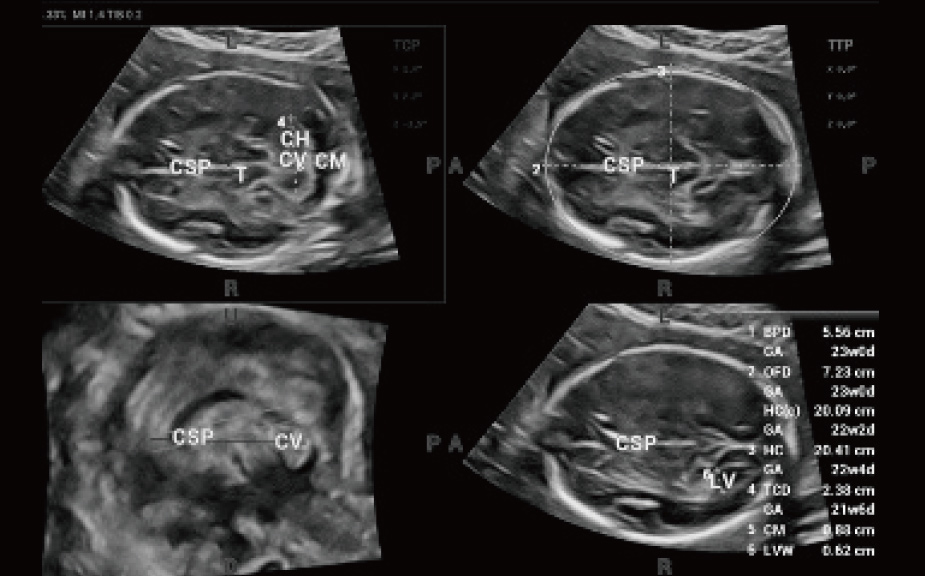

Con tecnologia ZST+

La piattaforma ZST+ rappresenta uno straordinario balzo in avanti nella tecnologia degli ultrasuoni, passando dal beamforming convenzionale all'elaborazione dei dati di canale. Questa innovazione rivoluzionaria supera i tradizionali compromessi tra risoluzione spaziale, risoluzione temporale e uniformit├Ā dei tessuti, dando vita a una qualit├Ā d'immagine senza pari che consente infinite soluzioni di imaging.

Intelligenza completa orientata allo scenario clinico

L'innovativa soluzione Smart Scene 3D consente l'identificazione automatica delle caratteristiche dei tessuti e fornisce una diagnosi specifica per i diversi distretti di esame durante l'intera procedura. Questa innovazione aumenta lŌĆÖaccuratezza e la sicurezza diagnostica, migliorando lŌĆÖefficienza.